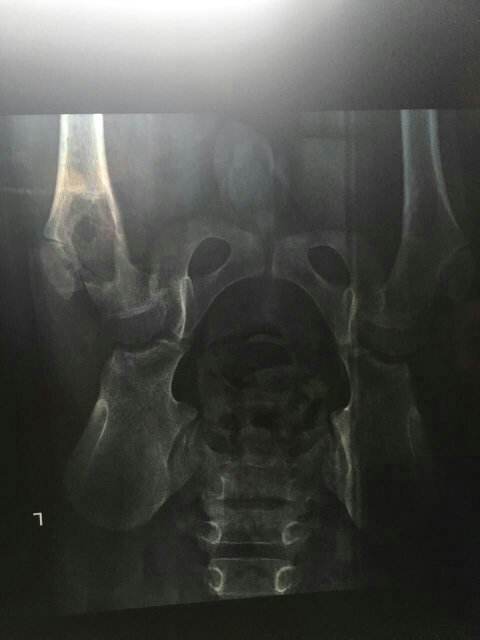

请问这是不是髋骨部分的骨囊肿?我家孩子11岁了,刚检查完X光 点击展开 匿名用户 2016-05-07 17:55 满意回答 您好,目前从片子上看很像,不过需要排除骨巨细胞瘤,建议您积极治疗,骨肆峡禁囊肿不积极治疗也是容易行饥造成骨脑院折等不良影响的! 张颖8818 2016-05-07 18:32 宝宝知道提示您:回答为网友贡献,仅供参考。 相关问题 两个月的宝宝左腿髋骨先天性发育不良,需要治疗?医生说孩子走路的时候去复查…我害怕到时候错过了最佳治疗时间对孩子以后走路有影响…有X光片和诊断结果…急急急… 三个月的婴幼儿臀纹不齐到医院拍x光所见:双髋骨盆结构完整,未见明显异常蜜度影,双髋骨关节基本在位 小孩一侧髋骨疼痛拍x光没问题是怎么回事?